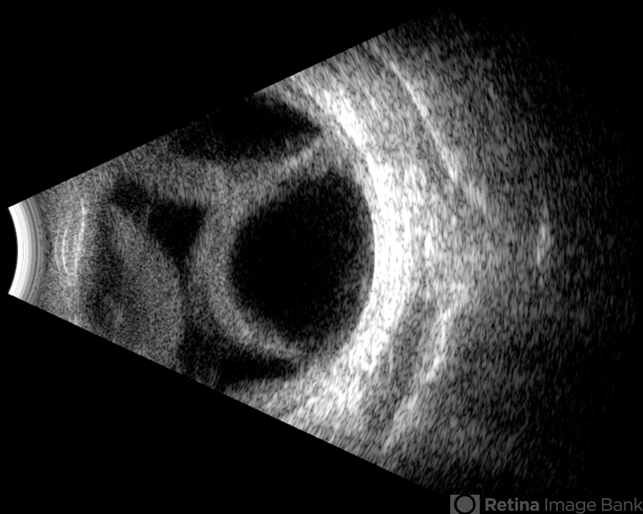

- Kissing Choroidal Detachment

- Cross-section of a B-mode ultrasound showing a kiss-shaped choroidal detachment; three lobes, giving the appearance of three kisses.